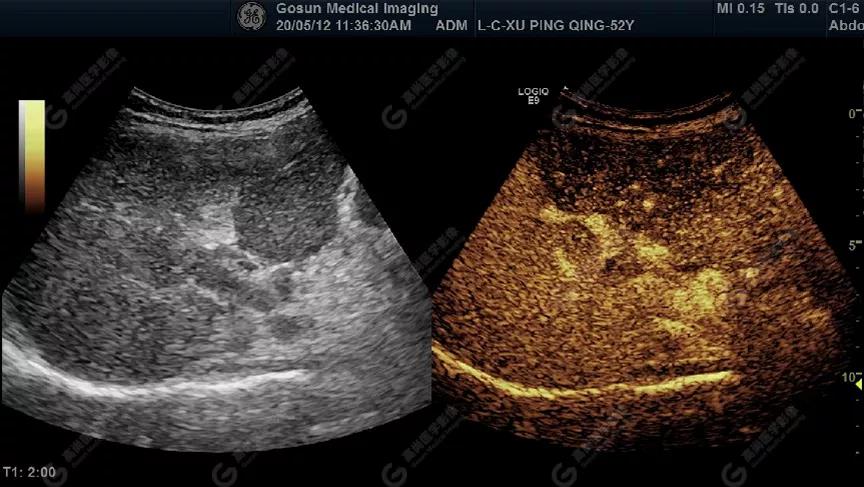

超聲造影顯示門靜脈內(nèi)低回聲呈高增強(qiáng)

延遲期肝S7局部回聲減低,范圍約82mm×50mm

內(nèi)見范圍約13mm×16mm低增強(qiáng)區(qū)

肝包膜不光滑,實(shí)質(zhì)回聲增粗,不均勻,以右葉顯著,肝內(nèi)可見散在高回聲結(jié)節(jié),最大約7mm×5mm,邊界清,形態(tài)規(guī)則,CDFI顯示高回聲結(jié)節(jié)未見明顯異常血流信號。門靜脈主干內(nèi)徑約14mm,門靜脈右支管腔內(nèi)見實(shí)性低回聲,大小約23mm×14mm,邊界不清,形態(tài)不規(guī)則,局部與肝組織分界不清,CDFI:門靜脈主干血流緩慢,左支血流充盈好,右支血流充盈缺損,低回聲內(nèi)未見明顯血流信號。超聲造影:經(jīng)左側(cè)肘靜脈團(tuán)注超聲造影劑sonovue2.0ml。肝組織開始增強(qiáng)時(shí)間8秒,病灶開始增強(qiáng)時(shí)間11秒,邊界清晰。脈期呈均勻高增強(qiáng),至門脈期和延遲期消退為低增強(qiáng)。延遲期肝S7段局部回聲減低,范圍約82mm×50mm,內(nèi)見一低增強(qiáng)區(qū),范圍約13mm×16mm。